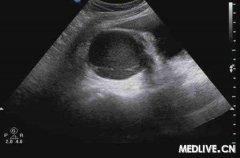

子宫内膜回声不均匀

子宫内膜回声不均匀是导致子宫内膜异位症发生的一种病因,该症状主要是指女性正常月经期间,子宫内膜对卵巢不能产生正常的反应。那么,什么是子宫内膜回声不均?…